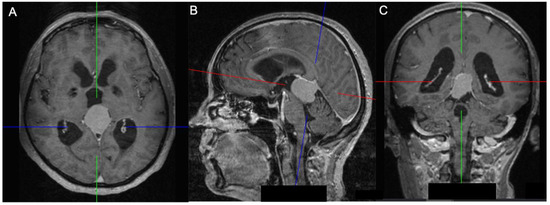

2.2. Volumetric Analysis, Vascular Features, and Tentorial Angle

| Tentorial angle | 49.6 (±6.2) | |